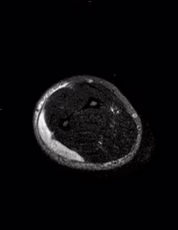

En el tejido celular subcutáneo del codo, tercio proximal y medio del antebrazo existe una colección superficial a la musculatura que tiene intensidad de señal heterogénea por zonas de menor intensidad de señal hacia la periferia, tiene medidas aproximadas de 19 x 5.4 x 1.2 cm con un volumen aproximado de 64.39 cm³.